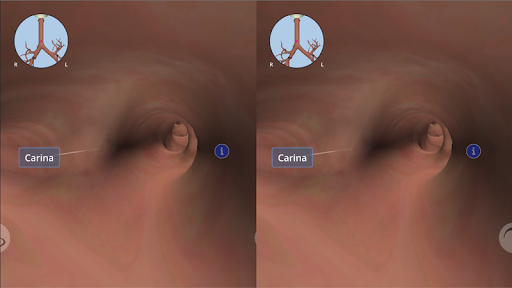

En utilisant la réalité virtuelle, vous serez capable de naviguer le long des structures anatomiques, devenant une partie de l'anatomie humaine: circulatoire, respiratoire, digestive, urinaire, lacrymale et système reproducteur féminin.

Anatomyou VR peut être utilisé dans deux modes différents: Réalité Virtuelle et Plein Écran.

En mode Réalité virtuelle, un appareil mobile (smartphone) doit être inséré dans un gadget de réalité virtuelle pour profiter d'une expérience totalement immersive. L'utilisateur peut interagir avec les commandes de navigation et les éléments d'information anatomiques en les visant.

Bien qu'il offre la meilleure expérience lorsqu'il est utilisé en mode réalité virtuelle, l'utilisateur peut également profiter et apprendre avec cette application mobile en mode plein écran, sans les besoins d'un gadget de réalité virtuelle.